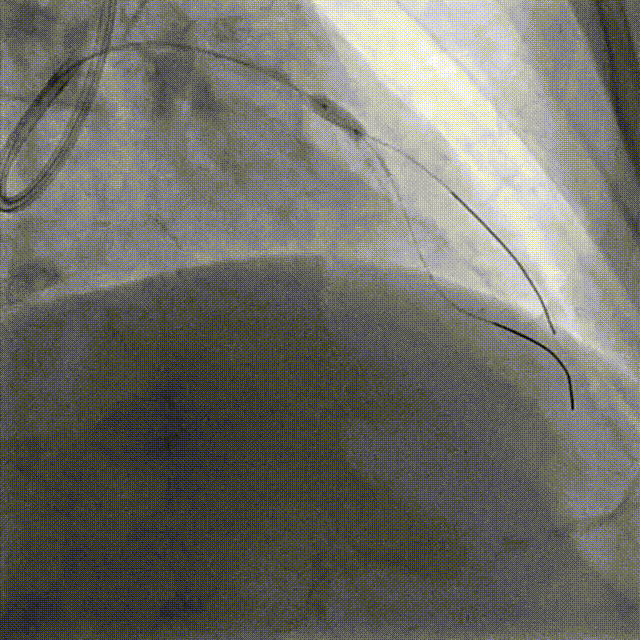

Lesion preparation NC 2.5*12mm → Cutting balloon 4.0*10mm @ 12atm

Angiography & DCB Angioplasty DCB 4.0*20mm @ 8atm, 60s